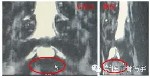

本病例為作者博士課題所進行的研究,使用磁共振脊髓成像術(shù)(MRM)能夠根據(jù)觀察到硬膜囊內(nèi)腦脊液充盈改變,直接判斷硬膜囊所受壓迫及程度。硬膜囊受到壓力時,其所含腦脊液受阻減少或消失,這種解剖學(xué)特點就決定了其是一個天然的壓力感受器。

治療前MRM椎管三維重建圖像,顯示腰椎管狹窄患者由于椎管狹窄硬膜囊中斷。

脊柱定點旋轉(zhuǎn)復(fù)位法治療后,MRM椎管三維重建圖像顯示腦脊液通過狹窄階段使硬膜囊末端明確延長,受壓硬膜囊較治療前明顯充盈,由此推測脊柱定點旋轉(zhuǎn)復(fù)位法可以使硬膜囊所受壓力減小,從而解除或緩解椎管狹窄癥狀。